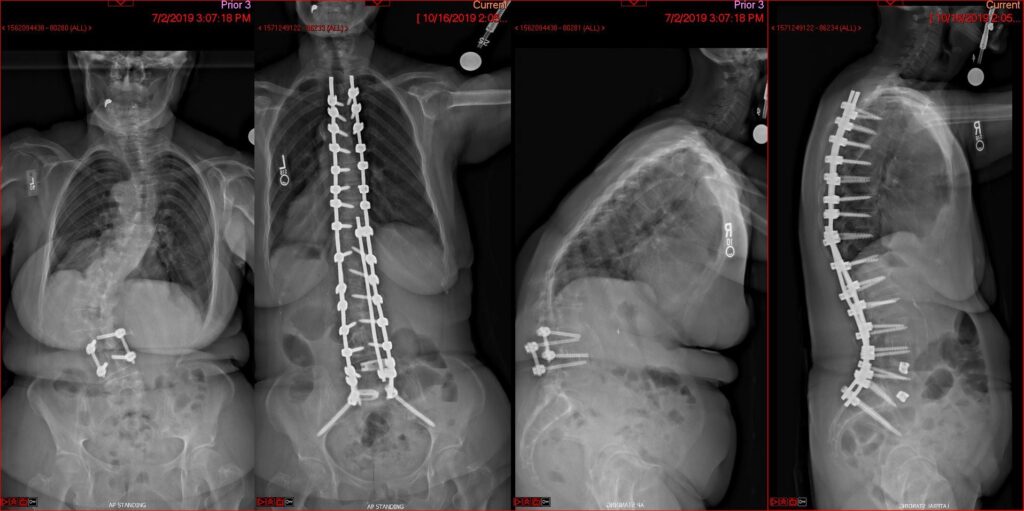

Deformity Surgery